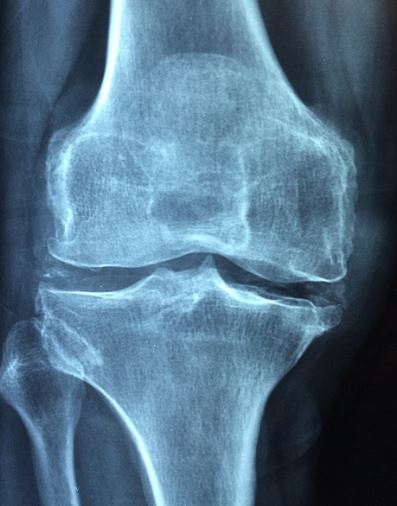

- 건강보험급여 '인공관절치환술 (슬관절)' 인정 기준에 준하는 환자